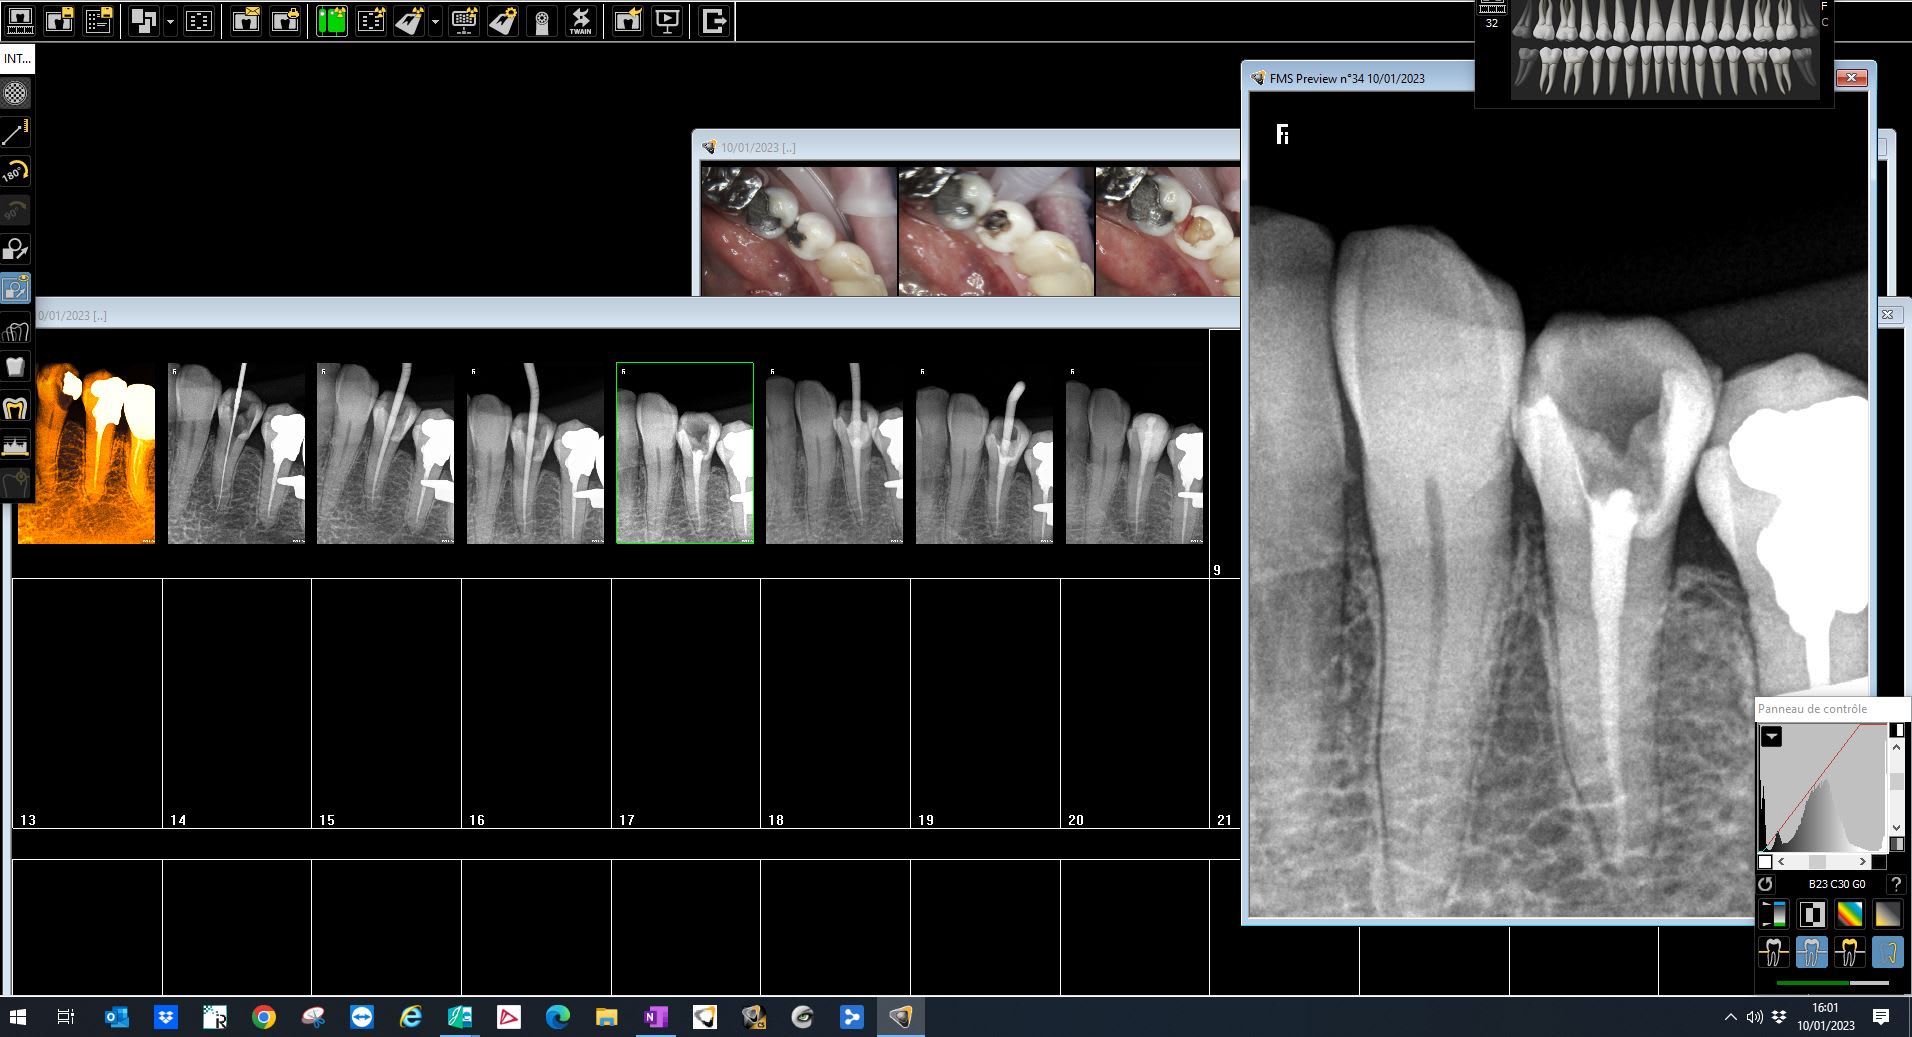

chicot29

Radio bio ceram en place. Je t'en collerais moi de la flotte. -)

> Radio bio ceram en place. Je t'en collerais moi de la flotte. -)

je pense que les dentistes qui prennent autant de radio per-op pour l endo ne sont pas sûr de ce qu ils font... ;)

Ne jamais avoir de certitudes. J'aime bien que la bio ceram aille à l'apex avant de sceller le cône.

Est ce que cotes la radio ? cad endo bio 3rx , pré, cône en place, post + radio perop?